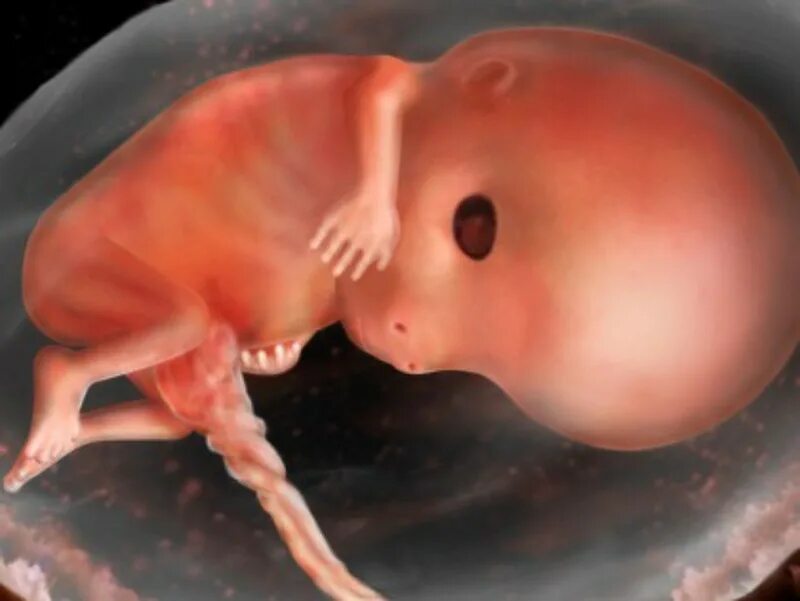

Куда девается эмбрион